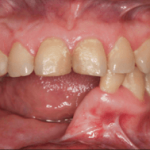

The conventional approach is completely based on the expertise and experience of the clinician. It includes simultaneous resection of the mandibular pathology as well as the harvesting of the fibular graft. This is done on the basis of manual measurements, making it not 100% accurate. The resection is then followed by the surgical reconstruction of the mandible by harvesting the fibular graft (image 3). Before the placement of implants the patient is asked to wait for a period of 3-5 months for the graft to get accepted.

After the acceptance and healing of the graft, a second surgery is conducted to place the implants; followed by another waiting period of 3-6 months for the osseointegration of the implants. The process of fabrication for the prosthesis beings after this; thereby increasing the time frame required for the complete rehabilitation to 9-12 months.

Drawbacks of conventional approach

Long waiting period till satisfying function and esthetics are achieved.

Formation of a thick layer of soft tissue post the first surgery hampers the placement of implants; in such cases “Debulking” of the soft tissue is necessary.

Manual measurements used for resection make it difficult to reach optimal positioning of implants.

Each surgical intervention increases the risk of infection.